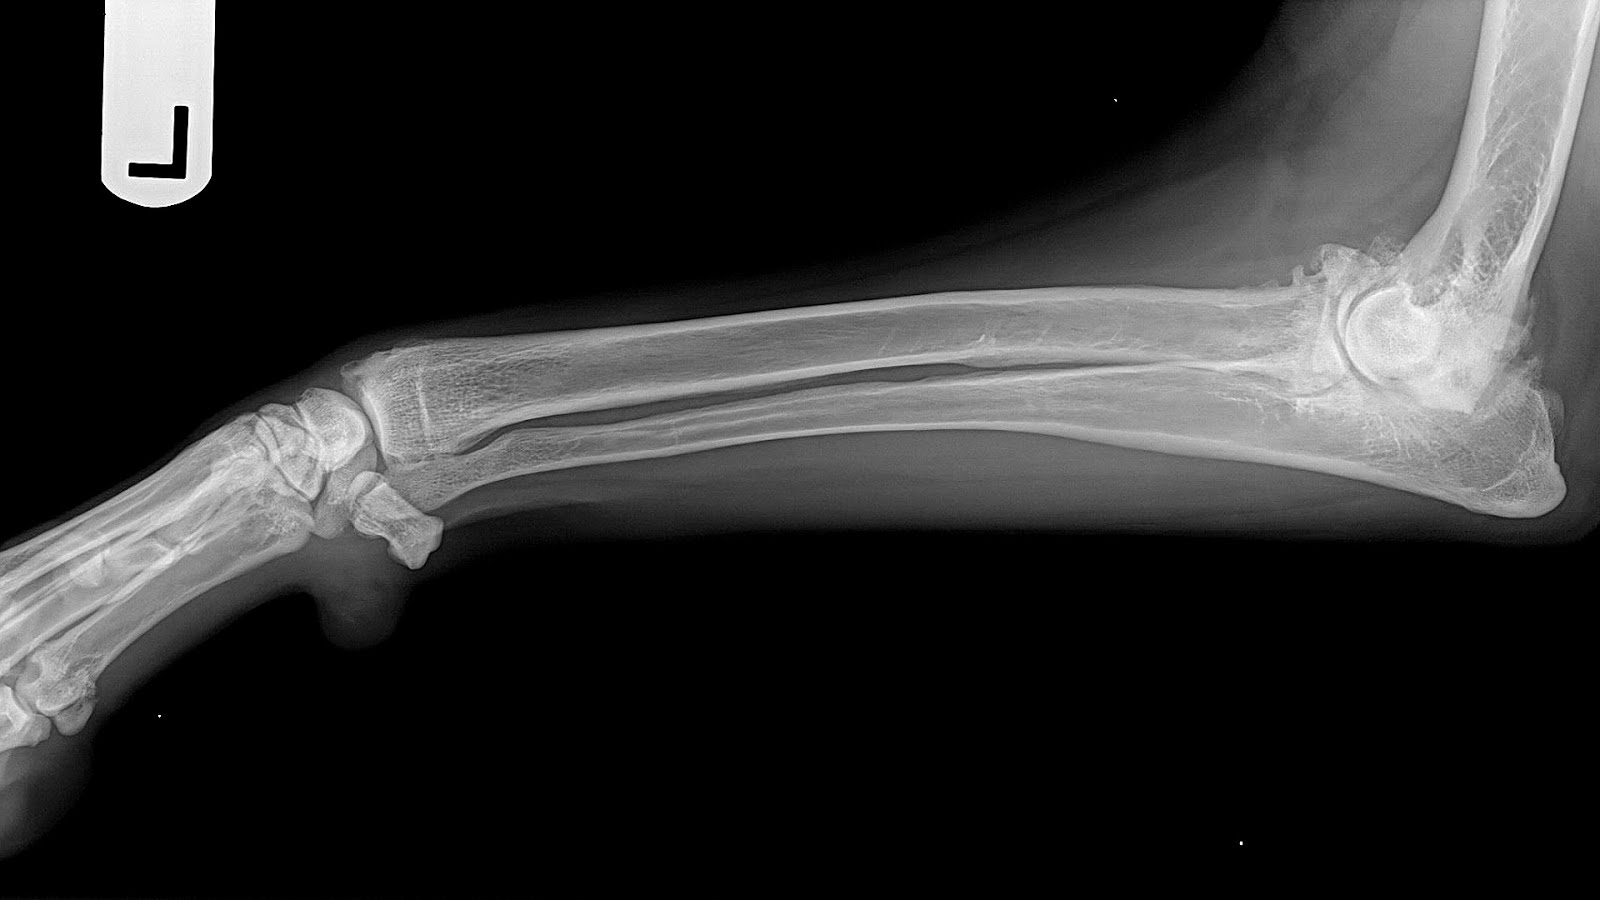

Dog Arthritis Canine Arthritis Resources and Education Arthritis in